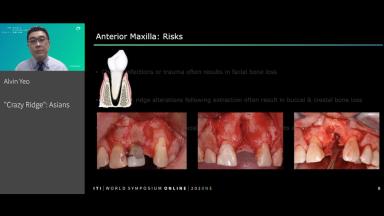

Following extraction, the tooth socket undergoes a healing process and series of changes, which include remodeling of the bone and alteration of the alveolar ridge dimensions. Management of the extraction socket can be challenging, especially in the esthetic zone. It has been documented that within 12 months of tooth extraction an average of 50% of resorption of the alveolar ridge can be expected to occur. Recently, an increasing body of evidence has reported that a substantial number of subjects from the Asian population demonstrated increased tooth-root-to-alveolus angulation. These data suggest that an impact from the management of the extraction socket defect and the implant placement timing must be considered due to an anatomic variation from the Caucasian population.

- recognize the potential additional risk presented by tooth-alveolus angulation when planning for implants in the anterior maxilla

- describe the relevant anatomic and surgical considerations for the Asian population with an emphasis on the anterior maxilla